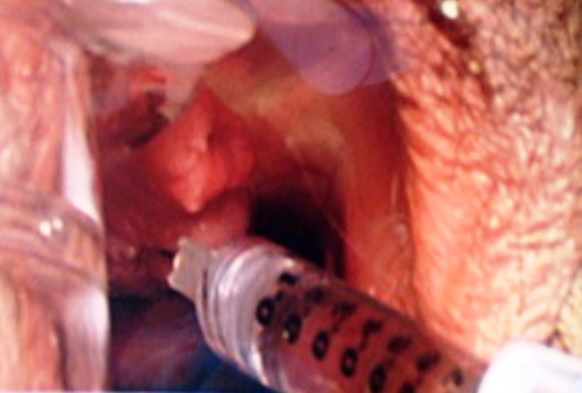

El aumento del punto G o G SHOT es una técnica que se realiza mediante la inyección de submucosa en la pared anterior del canal vaginal, específicamente en el punto medio, entre el borde posterior del pubis y el labio anterior del cuello uterino (en caso de no existir cuello uterino, de 2 a 3 cm detrás del pubis). Esta técnica ha sido practicada con distintos productos como son: lipotransferencia o grasa propia y el ácido hialurónico.

Actualmente, la inyección de ácido hialurónico de alto peso molecular es la mejor opción para procedimientos realizados en esta zona y no es una técnica nueva, ya que este componente también es usado en la cirugía urológica con el fin de tratar la incontinencia urinaria de esfuerzo